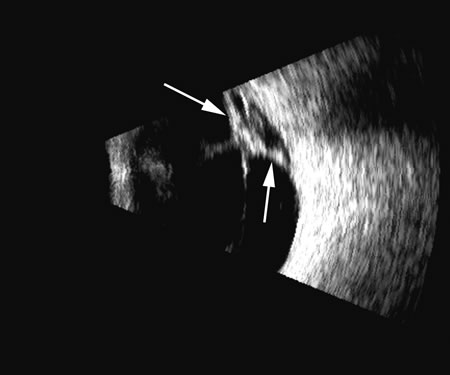

Fig. 7. This B-scan ultrasonogram demonstrates retinitis proliferans with typical vitreous membrane attaching to the proliferative membrane (arrows) that can resemble a traction detachment. Scanning at right angles helps distinguish proliferative membranes from retinal traction membranes, as they have less reflectivity than retina.

Fig. 8. A retinal detachment (arrow) is very easily detected as a high-amplitude, usually relatively rigid or gently wafting structure connecting always to the optic nerve head in a complete detachment, and usually traceable anterior to the ora serrata. Variations of this pattern can be seen, depending on the plane of the cut and the extent of the detachment, but the height of the echo on A-scan should always be maximal in order to differentiate retina from other, similar membrane formations.